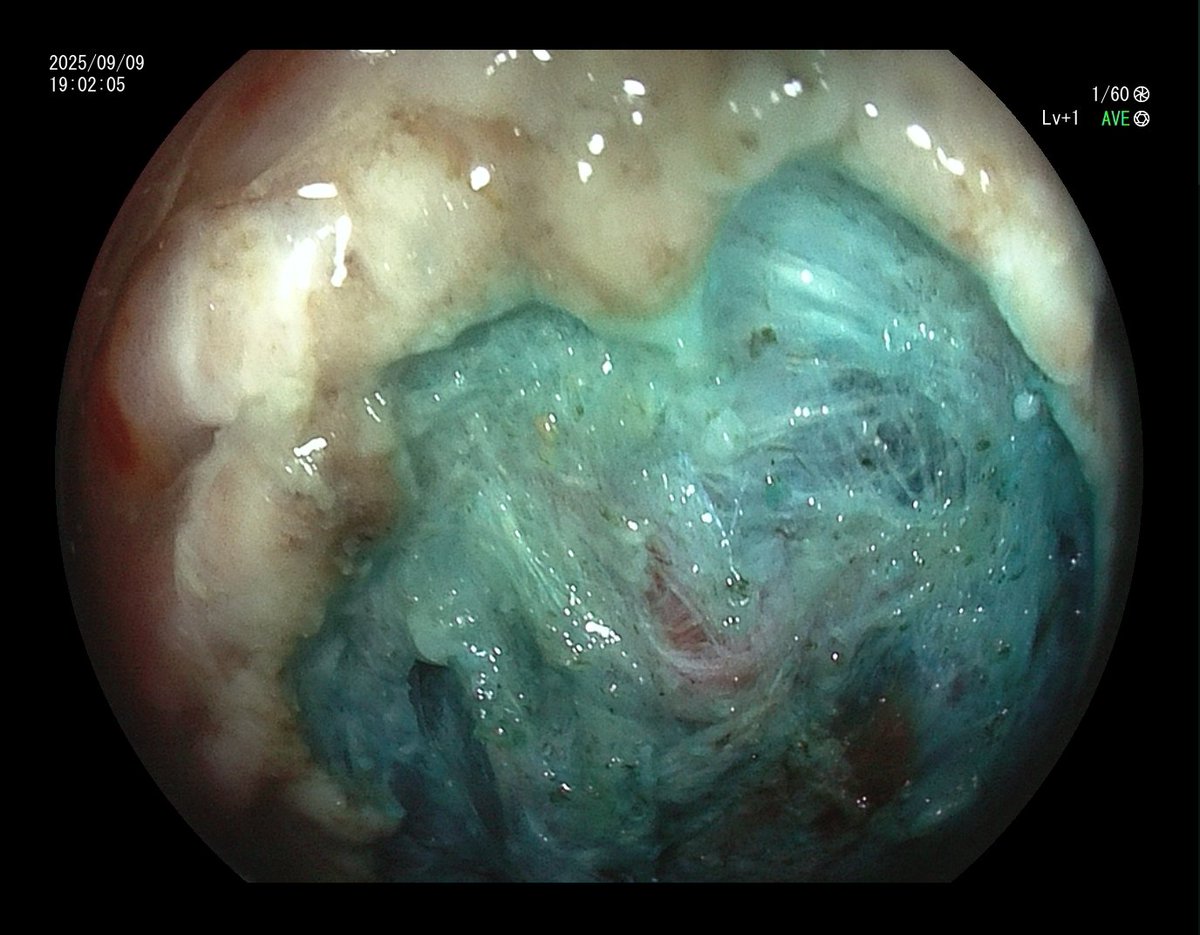

1. Antrum, low grade dysplasia. Removed via ESD. Specimen 43x32mm / dysplasia 20x13mm. R0